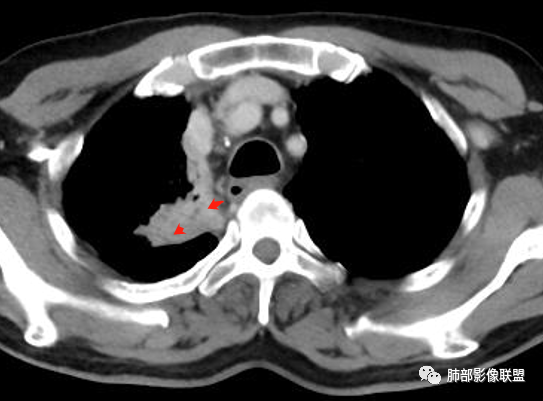

内部支气管近端狭窄,远端粘液栓

内部血管也通畅

不踏实的是这里稍膨隆